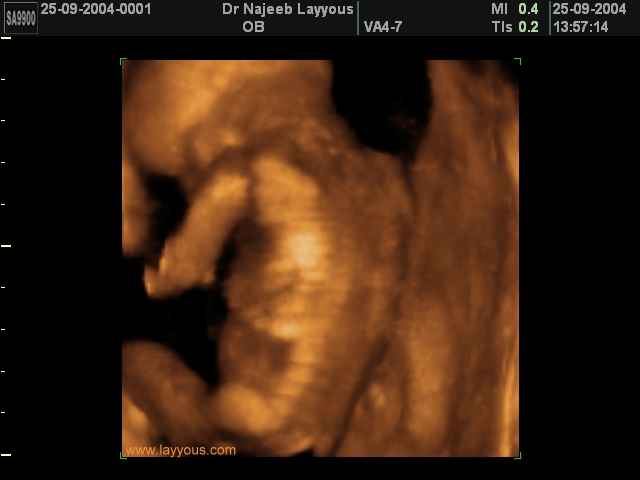

- لقطات فيديو للجنين بجهاز الموجات فوق صوتية رباعي الأبعاد

- صور جانبية لرأس الجنين

- صور لتصرفات الجنين داخل الرحم

صور لأعضاء الجنين بجهاز الموجات فوق صوتية ثلاثي الأبعاد | الدكتور نجيب ليوس